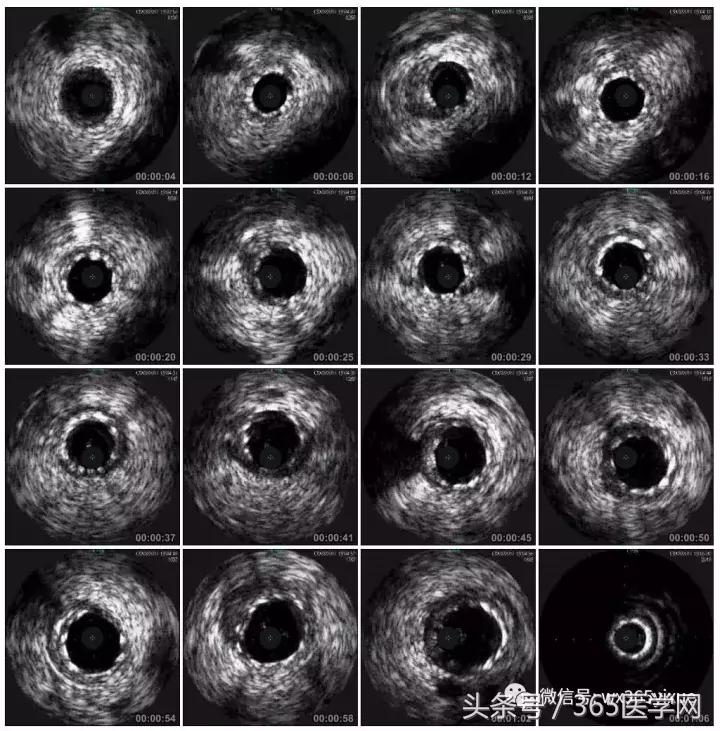

支架术后IVUS

小结

明确IVUS在CTO介入的重要性,

Guidezilla辅助下的ReverseCART更加高效,

Knuckle导丝技术在CTO介入中的使用。